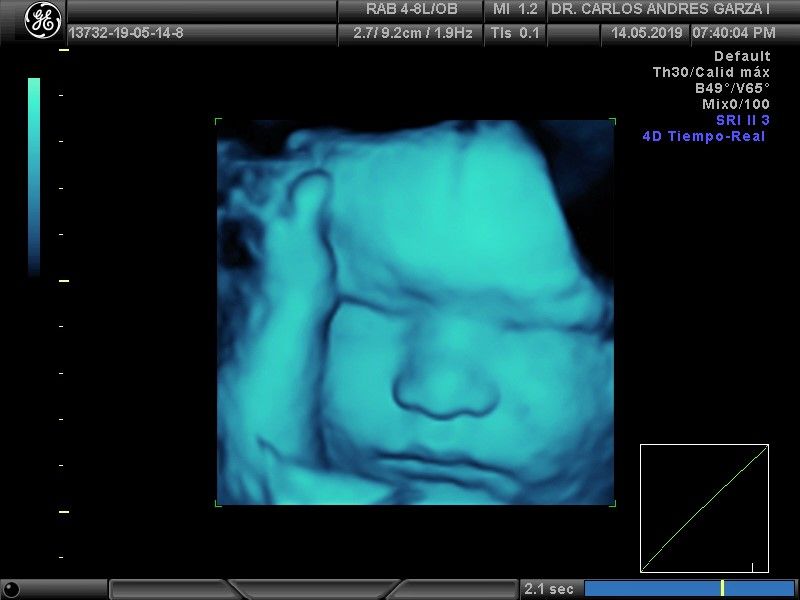

Ultrasonido 4D

!Conoce a tu bebé hoy¡ Se trata de la última tecnología en ecografía o ultrasonido a nivel mundial, que consiste en un procesamiento de reconstrucción digital de imágenes para formar una sola imagen en 4 dimensiones, permitiendo así poder visualizar cualquier estructura tal cual la estuviésemos viendo directamente el rostro de tu bebé, antes de nacer. Con esta nueva generación de tecnología del ultrasonido puedes observar datos mas detallados de su bebé, sus movimientos, gestos, risas, bostezo, etc... tal como si lo tuviera en sus brazos. En el pasado los papas no conocían la cara de su bebe hasta que naciera.